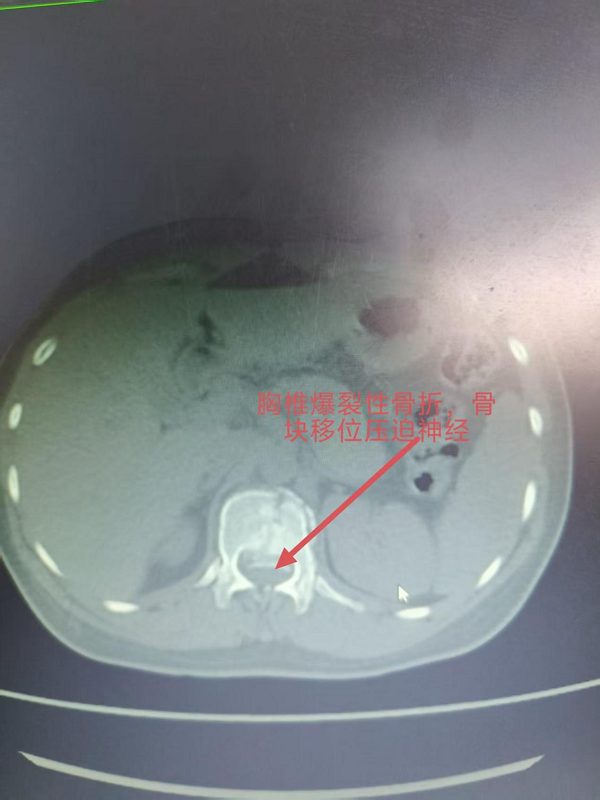

3. 为胸椎爆裂性骨折患者施后路切开复位、微创减压内固定术(四级手术),胸椎爆裂性骨折常因高能量损伤导致,骨折块可能突入椎管压迫脊髓,致残风险高。丁晔副主任医师团队采用微创理念进行减压,并完成了有效的复位与坚强的内固定,既解除了对神经的压迫,又最大程度地减少了手术创伤,为患者争取了最佳的神经功能恢复条件。

三台手术均顺利完成,患者术后恢复良好,标志着我院脊柱疾病微创化、精准化治疗迈上新台阶。